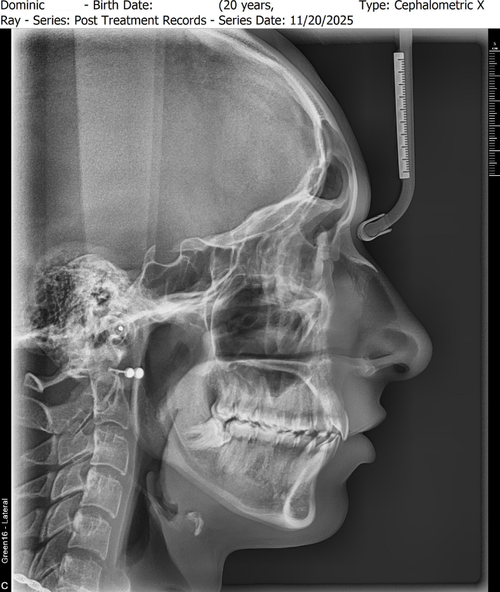

Just went to an orthodontist office and got x-rays for my recession. They basically said "your teeth are perfect and although your bottom jaw is recessed, your top jaw is recessed equally so they 'equal' out." The main guy told me that if I really wanted I could go the surgery route, and orthodontics can go hand and hand with surgery, but as for orthodontics alone i don't need/wouldn't benefit from anything. For example he was telling me about a surgery where they cut part of your jaw bone off and put it back on at a different angle.